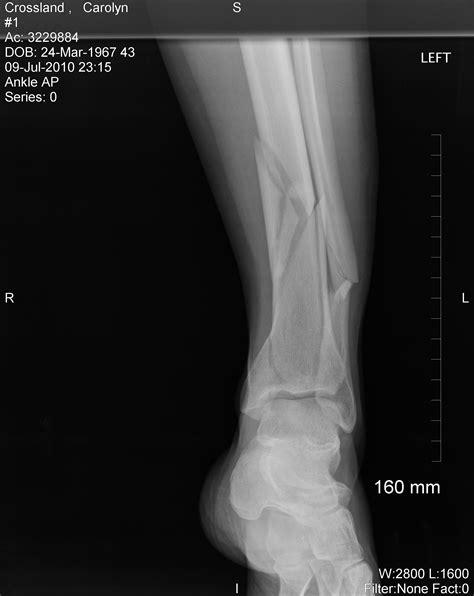

It is essential to seek medical attention as soon as possible. A healthcare professional will perform an X-ray to determine the extent of the fracture and develop an appropriate treatment plan.

A broken ankle occurs when one or more of the bones that make up the ankle joint are fractured. The ankle joint is composed of three bones: the tibia, fibula, and talus. Fractures can range from minor cracks to severe breaks that require surgical intervention. The broken ankle recovery time can vary significantly based on the type and severity of the fracture.